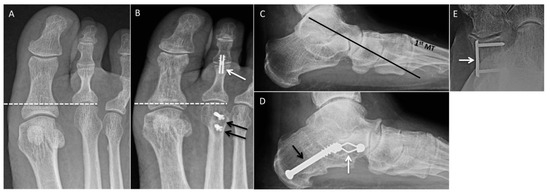

2.12. Single-Plane Translational Osteotomy

2.15. Medial Cuneiform Opening-Wedge Osteotomy